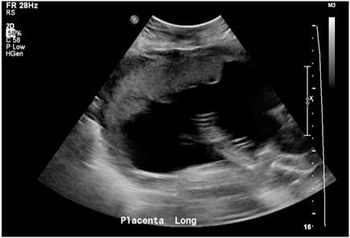

Case History: Pregnant female, 21 weeks 3 days gestational age, G2P1, experiencing severe peri-umbilical pain and a palpable bump just to the right of the umbilicus.